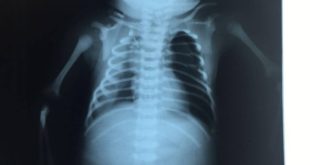

Bebê baleado na barriga da mãe pode não ficar paraplégico com procedimento, dizem médicos

A equipe médica responsável pelo atendimento do bebê baleado na barriga da mãe na última sexta-feira disse que o quadro de paraplegia do pequeno Arthur pode ser revertido. Os médicos se reuniram nesta segunda-feira com o secretário de saúde de Duque de Caxias para uma coletiva de imprensa. O bebê ...